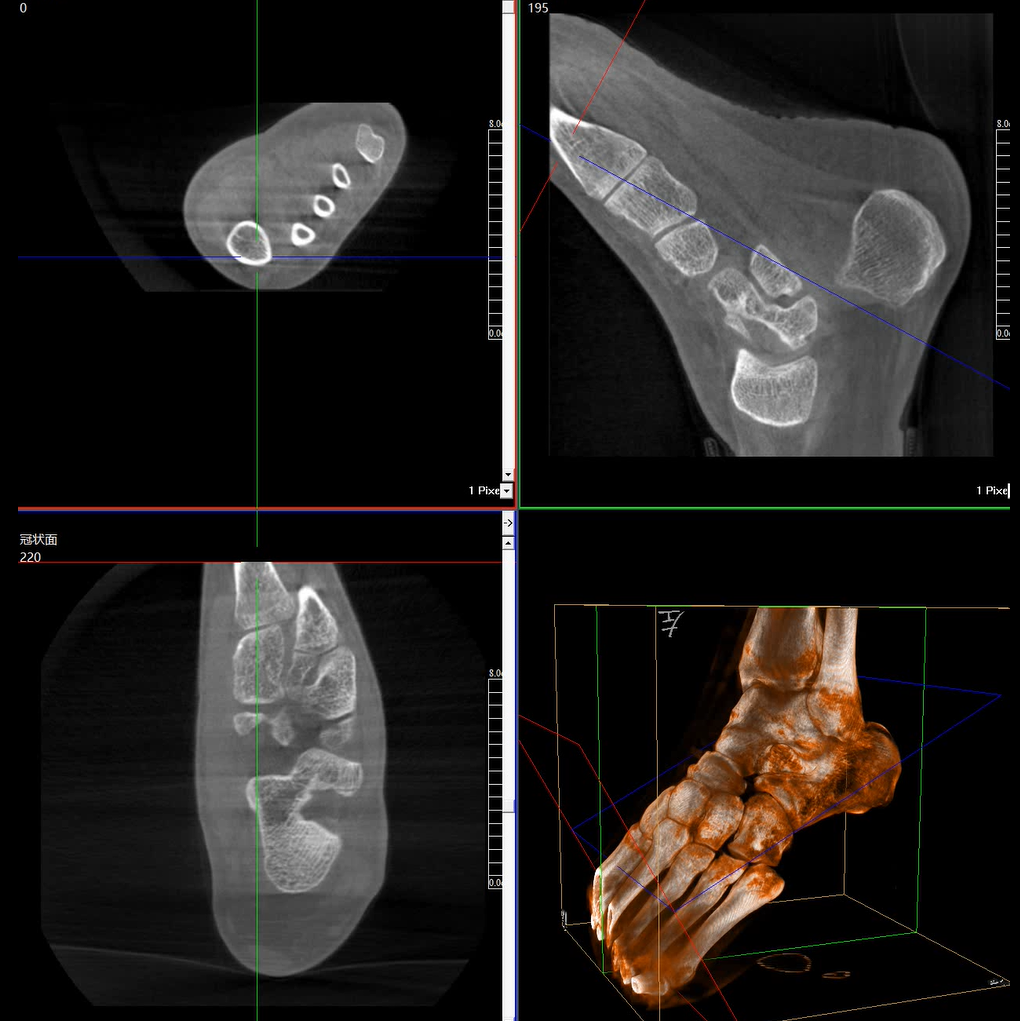

術(shù)中三維成像和橫斷面圖像提供多角度的手術(shù)診斷信息,輔助醫(yī)生進(jìn)行術(shù)中評估判斷,諸如骨折復(fù)位情況和內(nèi)植入螺釘?shù)某叽绾臀恢茫o助手術(shù)更好地完成。

提供更大的術(shù)中三維成像視野,采集更多圖像信息,可一次拍全全段頸椎、全段腰椎、七節(jié)胸椎、雙側(cè)骶髂關(guān)節(jié)、股骨頭及單側(cè)盆骨。